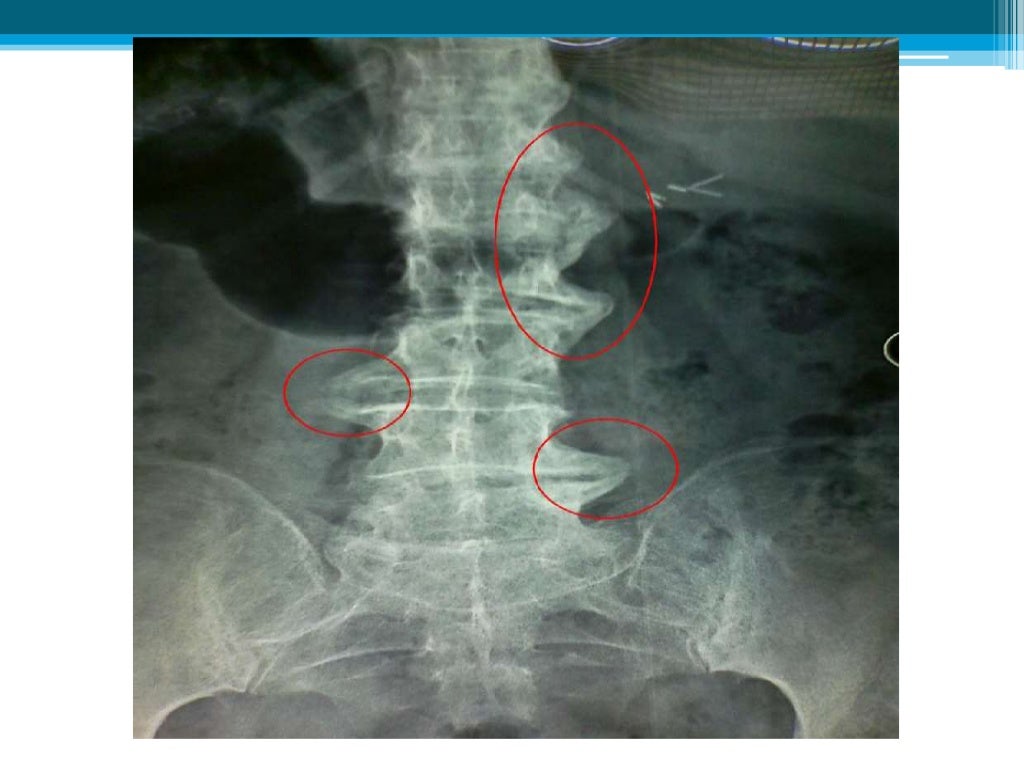

WebLa Espondilosis vertebral lumbar más que un diagnóstico, es un término genérico que usan los profesionales de la salud para referirse a afecciones de la. WebLas causas de esta afección pueden ser la edad, traumas, deformidad vertebral, infecciones, obesidad, sobrecarga, problemas posturales y otras alteraciones, como.

WebLa espondiloartrosis lumbar es la artrosis en la columna, que produce síntomas como dolor intenso en la espalda, causada normalmente por el desgaste de la articulación. No en. WebSi la espondilosis cervical comprime gravemente la médula espinal o las raíces nerviosas, el daño puede ser permanente. Hay un problema con la. WebLa espondiloartrosis es un cambio relacionado con la edad de los huesos (vértebras) y discos de la columna vertebral. Estos cambios a menudo se llaman enfermedad. WebLa espondiloartritis es grave. Pero con las estrategias de adaptación adecuadas y un plan de tratamiento coherente, la mayoría de las personas con la afección viven una vida plena. WebLa Espondiloartrosis o también Artrosis de Columna vertebral es una enfermedad degenerativa que afecta a los cartílagos de las articulaciones, provocando diversas. WebLa espondiloartrosis es una enfermedad degenerativa de la columna vertebral, que puede ser prevenida si se realza lo necesario en el momento indicado Es por esto, que aquí en. WebEl objetivo del tratamiento es aliviar el dolor y la rigidez, y prevenir o retrasar las complicaciones y la deformidad de la columna vertebral. El tratamiento de la espondilitis anquilosante es más exitoso antes de que la enfermedad cause daño irreversible. WebLa espondiloartrosis o artrosis (1) de la columna vertebral, es una patología degenerativa que causa desgaste del cartílago articular de las articulaciones.

WebLa espondiloartrosis, también llamada artrosis lumbar, es una degeneración de los cartílagos de la columna lumbar que genera dolor, rigidez y limitación del movimiento. WebLa espondiloartrosis lumbar se clasifica en cuatro grados, según la cantidad de daño que se haya producido en la columna vertebral. El grado I es el menos grave, y el grado IV es el. WebLa espondiloartrosis es una enfermedad degenerativa de las articulaciones que no presenta clínica hasta que los nervios está afectados y tampoco tiene cura. La.